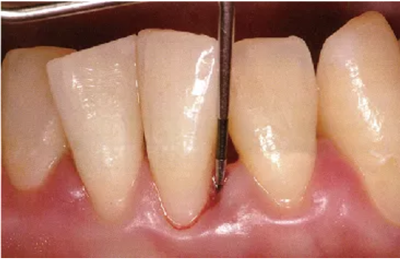

2、探針的插入

頰側(cè)、舌側(cè)的測定

探針要與牙軸平行插入。注意不要探針的尖端離開牙面。

● 頰側(cè)、舌側(cè)探針的插入

通常與牙軸平行插入

注意盡量讓探針貼著牙面。